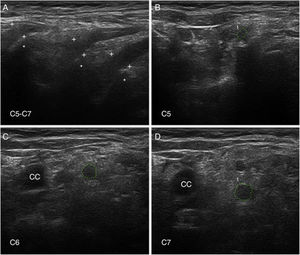

Ultrasonografía de nervioLa US de nervio es actualmente una técnica diagnóstica de rutina para el estudio de las enfermedades del SNP93. En nuestra serie de seis pacientes de SGB temprano, con cuatro casos catalogados como AIDP y los dos restantes como AMSAN, las principales alteraciones US ocurrieron en los ramos ventrales de los nervios cervicales, consistentes en incremento del área seccional transversa, borramiento de su anillo hiperecoico epineural, o ambos (fig. 8)15,94. En solo un 8,8% de los sonogramas de troncos nerviosos periféricos se observaron alteraciones inflamatorias, que afectaban sobre todo al nervio mediano.

Ultrasonografía (US) de nervios cervicales en la AIDP (mismo caso de la figuras 2 y 3); para hallazgos histológicos en el sexto nervio cervical, ver figura 1 y S1 en la referencia de Gallardo et al.15.

A)Sonograma sagital en el que se observa un borramiento de la envoltura epineural de los tres nervios escaneados (calibradores señalados con cruces). Los asteriscos indican las apófisis vertebrales transversas.

B-D)Sonogramas de los ejes cortos de los ramos ventrales de los nervios C5-C7, que han sido delimitados por trazos interrumpidos verdes. Las áreas seccionales transversas estaban significativamente incrementadas. Nótese la ausencia del anillo hiperecoico epineural, lo cual puede contrastarse con las imágenes normales en el trabajo de Haun et al.94. El edema inflamatorio endoneural (ver figs. 2C-D y 3) justifica el incremento del área seccional transversa, mientras que el componente inflamatorio epi-perineural (ver fig. 2E) responde del borramiento del anillo hiperecoico epineural.

A diferencia de nuestros hallazgos, otros autores han observado un incremento de las áreas seccionales de los troncos nerviosos periféricos en fases precoces del SGB, si bien solo el edema regresivo de los nervios C5-C6 parece correlacionarse con la mejoría clínica95-97. Dado que la US de nervio es una técnica dependiente de la pericia del explorador, son necesarios más estudios para determinar con mayor precisión su valor dentro del elenco de pruebas diagnósticas en el SGB98,99.